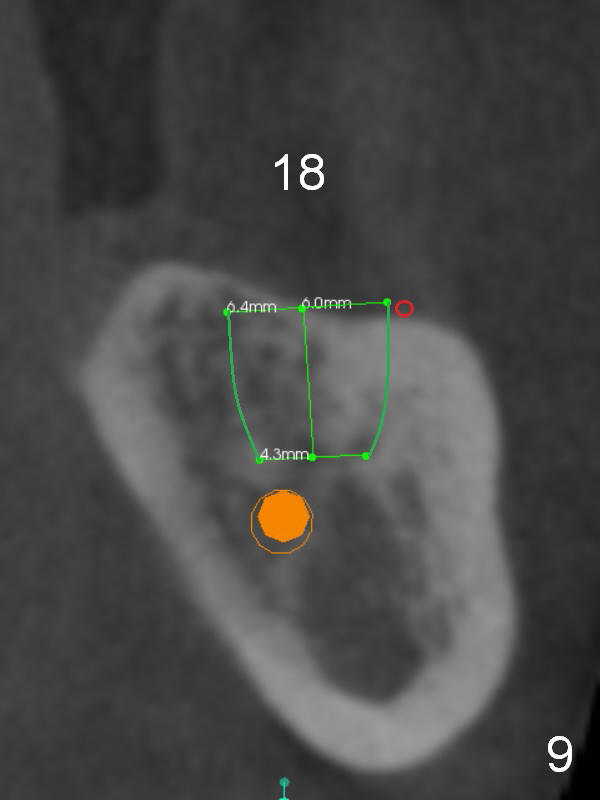

There is severe bone resorption around the distal root of the lower left 1st molar of the 56-year-old man (WG), while the loss of the 2nd molar is associated with limited bone height (Fig.1). A 5x14 mm implant will be placed at the mesial socket of #19 and 5.9 or 6.4x6 mm one is at the mesial site of #18 (Fig.7-9). Use a 2 mm pilot drill with 6 mm stopper from Sinus Master Kit (with extension) to initiate osteotomy at #18 immediately distal to the crown of #19, parallel to the long axis of the latter (Fig.2). After inserting a parallel pin at #18, extract the tooth #19 (Fig.3, antibiotic pending) and start osteotomy with a 2 mm pilot drill with 14 mm stopper (Fig.4). Insert the calibrated parallel pin at #19 (Fig.5) and measure the distance between the two parallel pins (approximately 10 mm, Fig.7). Sequential osteotomy and application of the Tatum taps (Fig.6 red rectangle) will push the septum distal (green arrow). As to #18 osteotomy, trephine, final and tap drills are to be used with control of the depth: 6 mm (Fig.7,9).